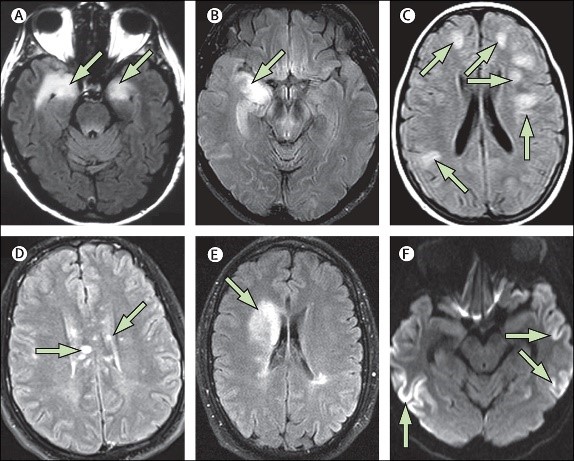

脑炎后的磁共振变化